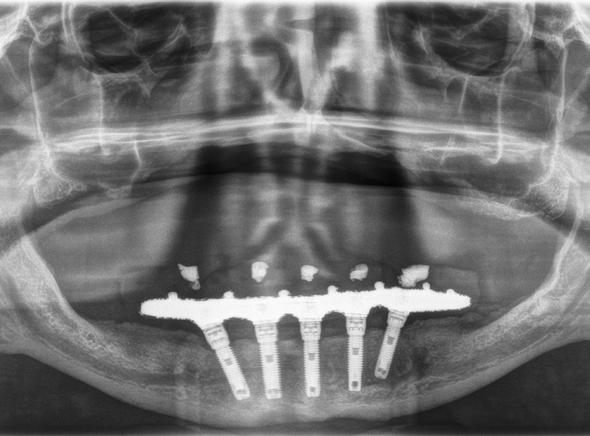

Figura 7­9. Cortes de planificación del cone beam donde observamos la extrema atrofia vertical y la posición en la que deberían situarse los dientes con una gran discrepancia entre esta posición y la base ósea. Vemos también como se planifican implantes extracortos de 5.5 mm de longitud en todas las localizaciones. Figura 10. Radiografía panorámica tras la colocación de los implantes.

En las Figuras 2­17 se puede observar uno de los casos incluidos en el estudio.

en hueso con técnicas de aumento previa, obteniéndose cifras menores para el grupo de los implantes extracortos (0.18 mm al año, 0.37 mm a los 3 años y 0.53 mm a los 5 años, con diferencias estadísticamente significativas (p<0,01 en los tres casos).1 En nuestra serie de casos, la pérdida ósea reportada para los pacientes tratados únicamente con

implantes de 5.5 mm de longitud fue de 0.21 mm en mesial (+/- 0.40) y de de 0.18 mm (+/- 0.42) en distal, por lo que son cifras similares, teniendo en cuenta que el seguimiento del estudio es de 31.9 meses. El metaánalisis que compara la pérdida ósea crestal en implantes cortos y en implantes de longitud mayor insertados en zonas de regeneración ósea1 también observa una mayor pérdida ósea crestal para los implantes del maxilar comparados con la mandíbula, pero no pudieron identificarse diferencias estadísticamente significativas, siendo concordante también con los datos arrojados por nuestro estudio.

La evidencia de que los implantes cortos ferulizados pueden presentar una predictibilidad similar a la de los implantes de mayor longitud, con un comportamiento biomecánico

Dentista y Paciente 54 Enciclopedia odontológica

Figura 11­12. Prueba del encerado para la realización de la prótesis provisional tras 6 meses desde la colocación de los implantes. Figura 13. Radiografía panorámica tras la colocación de prótesis provisional de carga progresiva. Figura 14 y 15. Planificación por CAD/CAM de la estructura de la prótesis definitiva y finalización de la misma con el cementado de coronas de disilicato sobre la estructura.